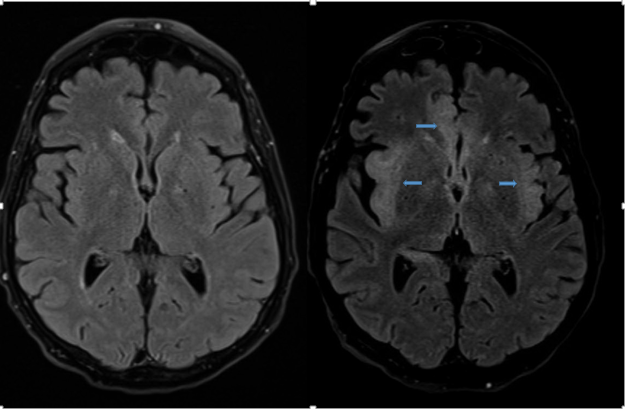

An infectious diseases specialist was consulted, and the patient was treated with intravenous acyclovir and antibiotics for pneumonia. A brain MRI was repeated on the seventh day of hospital admission, the results of which showed extensive cortical edema consistent with a diagnosis of herpes simplex encephalitis (HSE) (Figures).

Figures. T2-weighted fluid-attenuated inversion recovery MRI sequences on day 1 (top left and bottom left) and day 7 (top right and bottom right), the latter of which showed an extensive pattern of abnormal cortical edema suggesting underlying encephalitis in the inferior mesial frontal lobe, insular cortex, and mesial temporal lobe bilaterally (blue arrows).